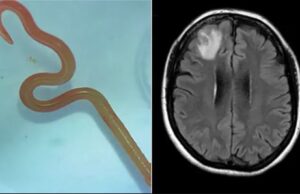

Σκουλήκι 8 εκατοστών αφαιρέθηκε από τον εγκέφαλο γυναίκας

Για πρώτη φορά στα χρονικά της ιατρικής, ένα σκουλήκι που κανονικά παρασιτεί σε πύθωνες αφαιρέθηκε ζωντανό από τον εγκέφαλο μιας άτυχης γυναίκας στην Αυστραλία.

«Θεέ...